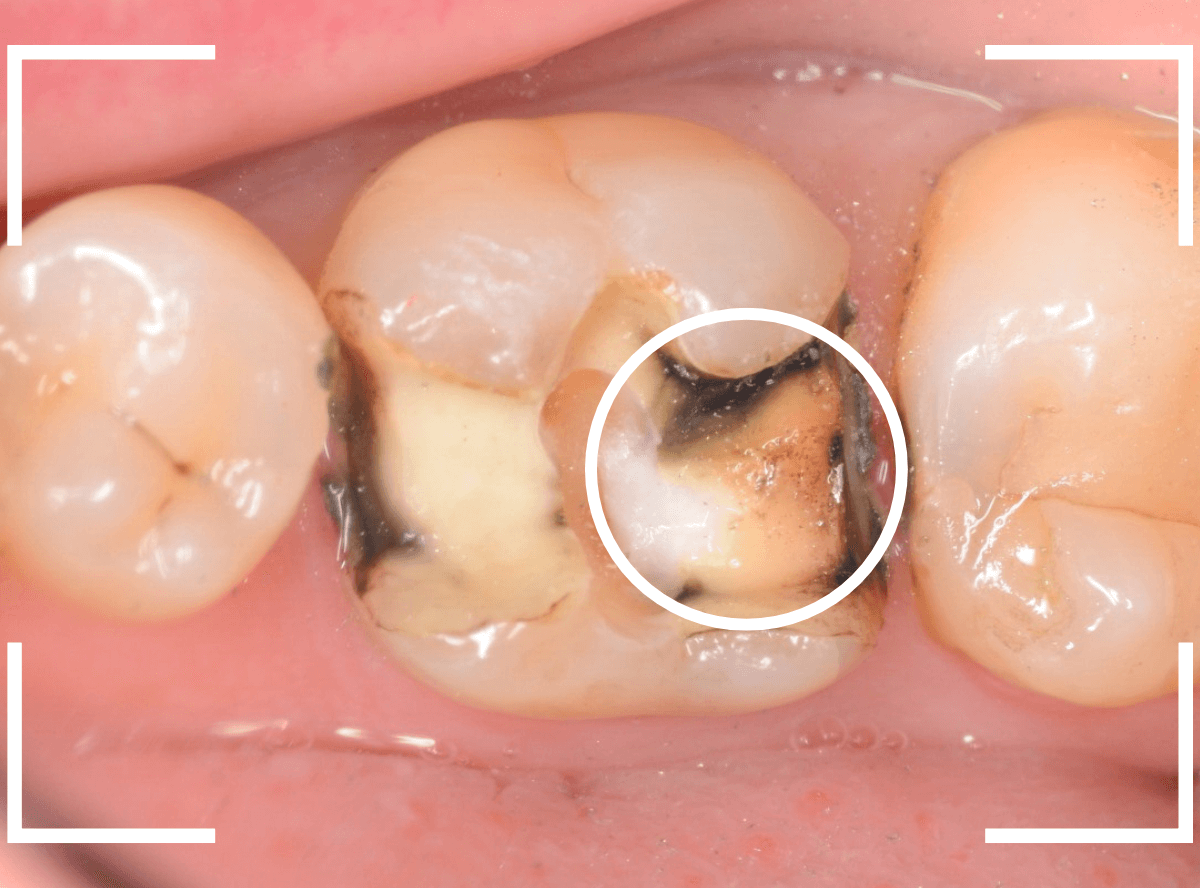

レントゲン写真では問題なさそうでしたが、メタルコアを除去すると、中は真っ黒でした。

このように、コアの中で虫歯が進行している場合もありますので、さし歯をやり直す際は、出来る限りコアも外して調べるようにしています。

虫歯を全て除去しました。

幸い、あまり多く削る事なく進められたので良かったです。